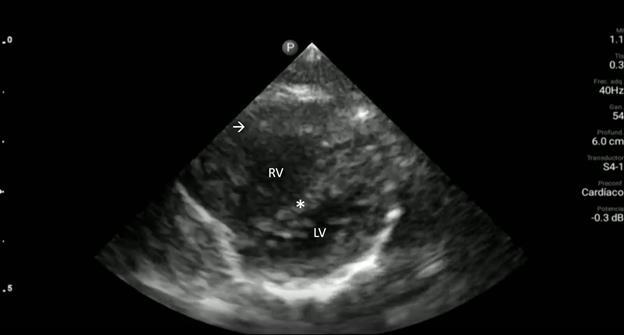

Upon closer inspection, parasternal long-axis view revealed a ventricular septal defect with an overriding aorta and RVH concerning for TOF (Image 2). Parasternal shortaxis cardiac view redemonstrated RVH with interventricular septal flattening indicative of right ventricular pressure

Image 2. Parasternal long-axis view of the heart highlighting the findings of a ventricular septal defect (*) with an overriding aorta (Ao) and right ventricular hypertrophy (arrow). LA indicates left atrium; LV, left ventricle; RV, right ventricle.

Video 1. Parasternal long-axis view of the heart. Ventricular septal defect (*); overriding aorta (Ao); right ventricular hypertrophy (arrow); left atrium (LA); left ventricle (LV) right ventricle (RV).